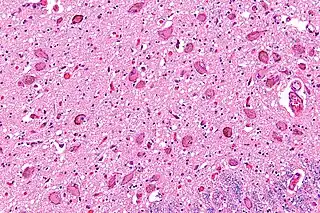

![]() Micrografía mostrando el locus cerúleo. (Tinción luxol fast blue). | ||